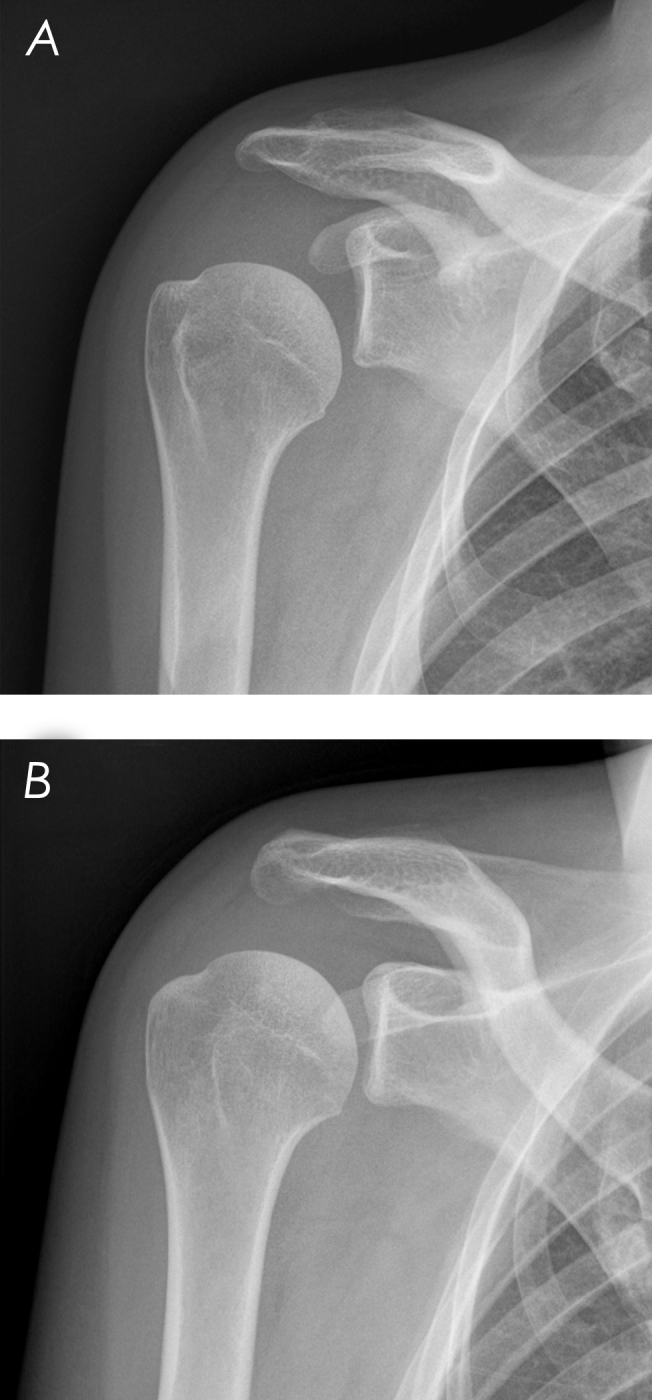

我们报告了一位31岁的免疫功能低下的女性,患有肩关节脓毒性关节炎和冈下脓肿,在关节内注射后出现继发于腋窝神经病变的瘫痪。12个月时,活动能力和正常功能恢复。这是首次报道的成人病例,强调免疫功能低下患者需要高度怀疑脓毒性关节炎,并强调有效的管理策略。

We present a 31-year-old immunocompromised woman with shoulder septic arthritis and an infraspinatus abscess presenting with paralysis secondary to axillary neuropathy after an intra-articular injection. At 12 months, mobility and normal functioning were restored. This first reported adult case highlights the need for high suspicion of septic arthritis in immunocompromised patients and emphasizes effective management strategies.